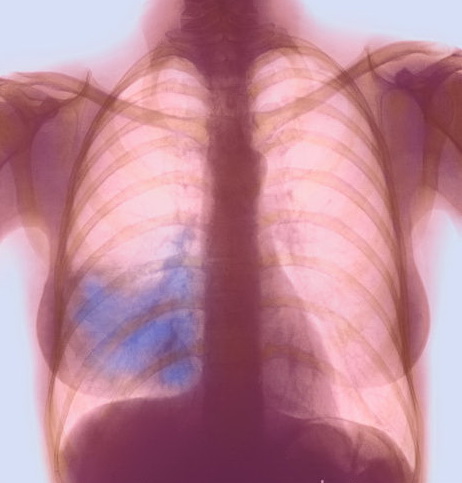

Пневмония ( воспаление легких)

Воспалительный процесс, который охватывает легочную ткань. Это могут быть небольшие очаги либо целая доля легкого. Отмечаются боли в грудной клетке, расположение которых соответствует патологическому очагу в легочной ткани. При поражении задних отделов органов вызывает боль между лопаток. Отмечаются и другие симптомы:

• высокий подъем температуры тела, значительное ухудшение состояния;

• кашель, одышка;

• поначалу кашель сухой, но затем начинает отходить мокрота.

Диагностикой и лечением пневмонии занимаются терапевты и пульмонологи. Диагноз устанавливается после проведения рентгенографического исследования грудной клетки в двух проекциях: прямой и боковой. Все больные с пневмонией должны быть помещены в стационар, назначается постельный режим, антибиотики, другие симптоматические лекарственные средства.

Плеврит

Воспаление плевры, которая имеет вид пленки и выстилает изнутри грудную клетку, покрывает легкие. При этом заболевании также могут возникать боли в разных частях грудной клетки, что зависит от места поражения. Соответственно, боль между лопатками является в данном случае признаком поражения задних листков плевры. Возникают и другие проявления:

• повышение температуры тела, нарушение общего состояния;

• одышка;

• боли в основном связаны с дыхательными движениями, они усиливаются при глубоком вдохе;

• имеется кашель, но он всегда сухой, мокрота не отходит.

Основной метод, при помощи которого устанавливается диагноз – рентгенография грудной клетки. Лечение плеврита осуществляется преимущественно в стационаре. Заболеванием занимаются такие специалисты, как терапевт и пульмонолог.